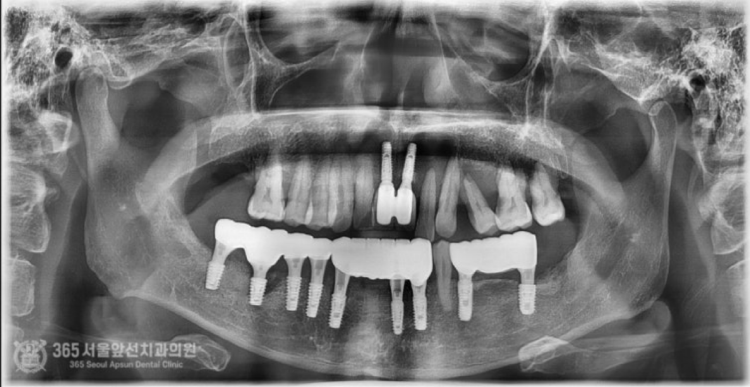

안녕하세요. 도화역치과 365서울앞선치과입니다. 오늘 소개해 드릴 치료 증례는 지인분의 소개로 찾아오셨던 환자분이십니다. 전체적으로 치아가 좋지 않으나 일단 아랫턱부터 치료를 완료하고 나서 윗턱을 치료받고 싶다고 하셨습니다. 바쁘게 사회생활을 하셔야 하는 환자분이셔서 발치와 동시에 뼈이식을 진행하며 임시치아까지 즉시 만들어 드렸습니다 ㅎㅎ 촬영일시: 2024.06.20. 처음 도화역치과 365서울앞선치과에 내원하셨을 당시 엑스레이 사진입니다. 전체적으로 잇몸뼈 소실 증상이 있고 치아 상태가 매우 좋지 않습니다. 일단 위쪽은 아래쪽 치료를 마무리 한 이후에 하기로 결정하셨습니다. 촬영일시: 2024.07.06. 발치와 동시에 뼈이식을 진행하면서 임플란트 식립까지 완료한 이후 엑스레이 사진입니다. 가지런히 식립된 임플란트 보기 좋습니다 ㅎㅎ 수술시간은 대략 30분 정도 걸렸습니다.